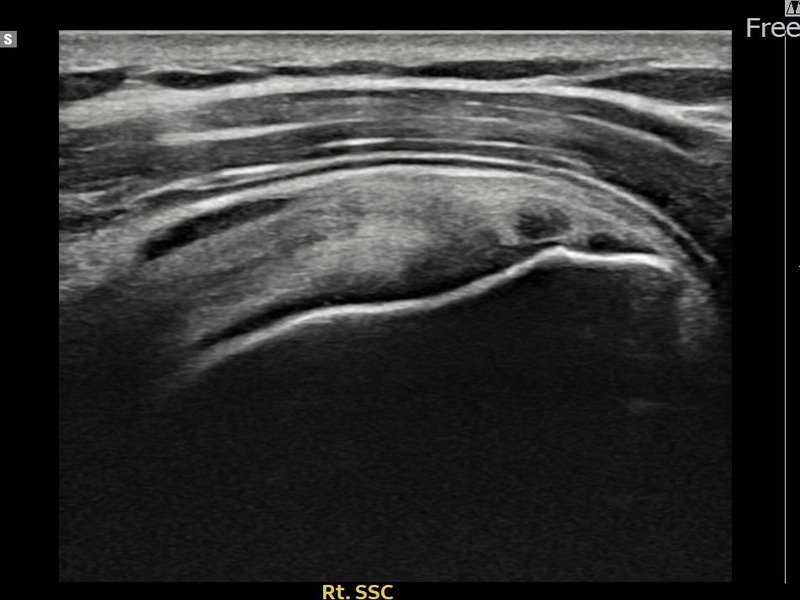

유ㅇㅇ님 · 우측 견갑하근건 관절면측 부분파열

우측 어깨 전방 통증과 팔 내회전 제한으로 내원하셨습니다. 초음파 검사에서 견갑하근건 관절면측 부분파열이 확인되었으며, 어깨인대 축소봉합술 후 힘줄 구조적 안정화가 이루어졌습니다.

유ㅇㅇ님 · 우측 견갑하근건 부분파열

우측 어깨 전방 통증과 팔 들어 올리기 어려움으로 내원하셨습니다. 초음파 검사에서 견갑하근건 부분파열이 확인되었으며, 어깨인대 축소봉합술 후 힘줄 연속성이 회복되고 어깨 기능이 정상화되었습니다.